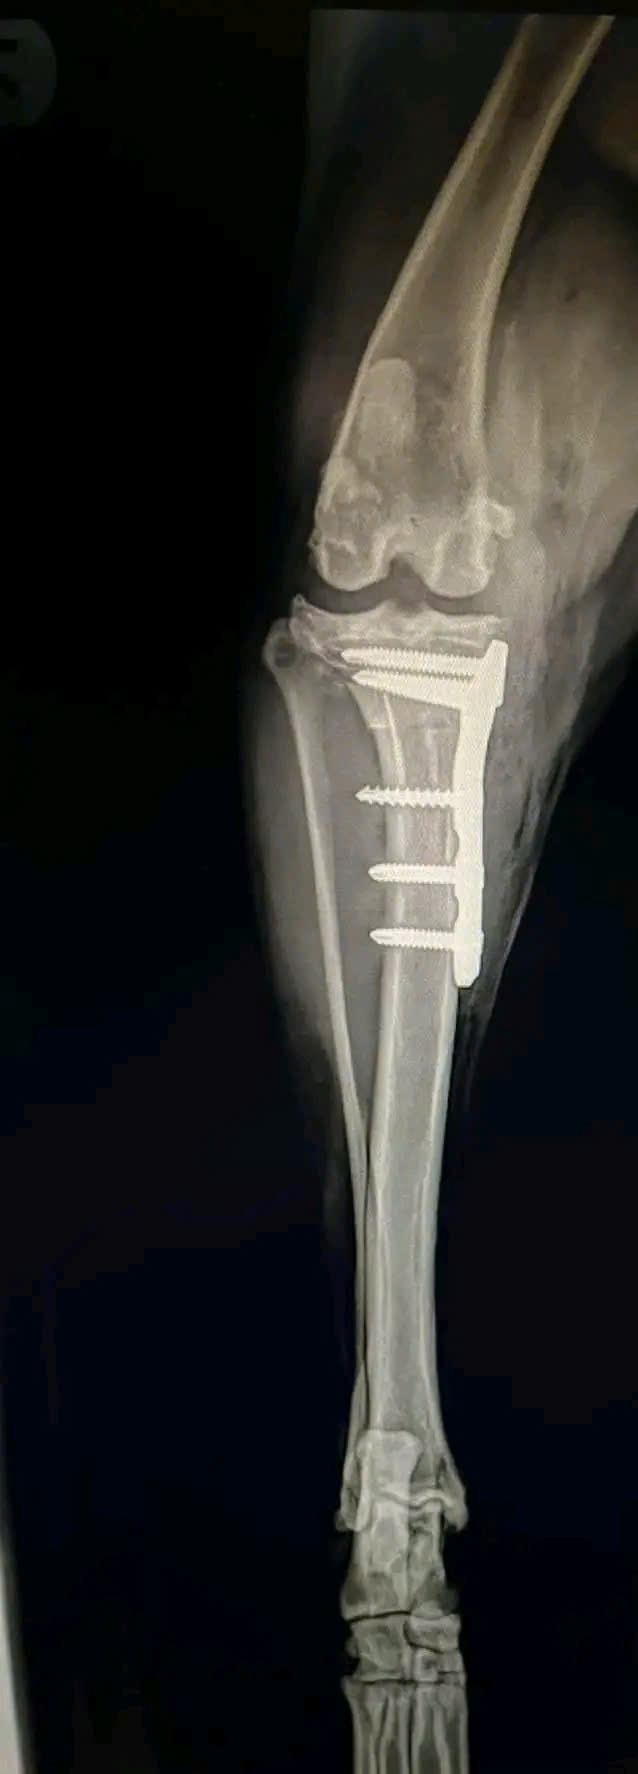

Hình ảnh thực tế

Khám phá không gian chăm sóc thú cưng chuyên nghiệp tại Bệnh viện Thú Y Gia Kiệm